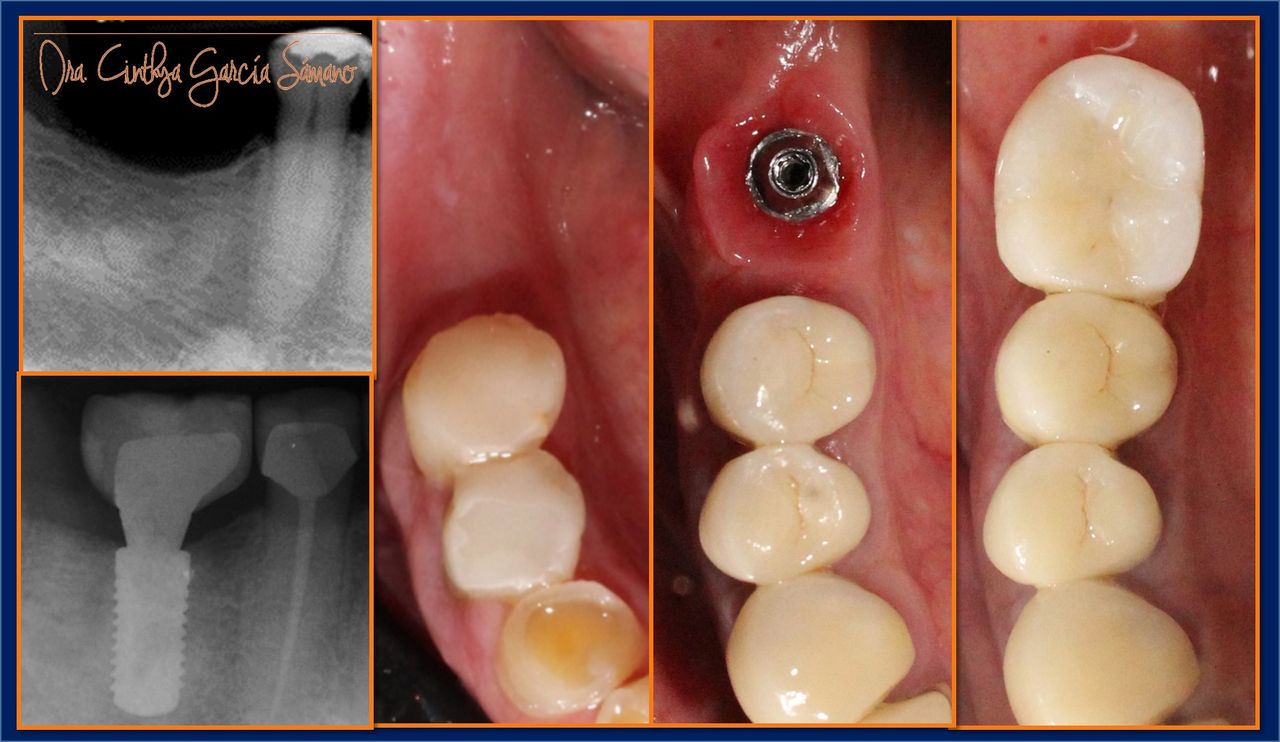

• Implantología dental

• Visita Odontología